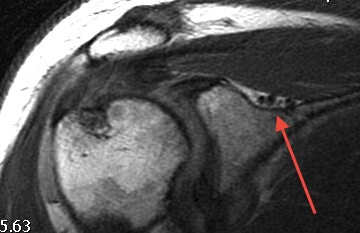

Most common type / in older patient with pre-existing spondylosis / OPLL

- hyperextension injury

- compression of the cord

- anteriorly by osteophytes

- posteriorly by infolded ligamentum flavum